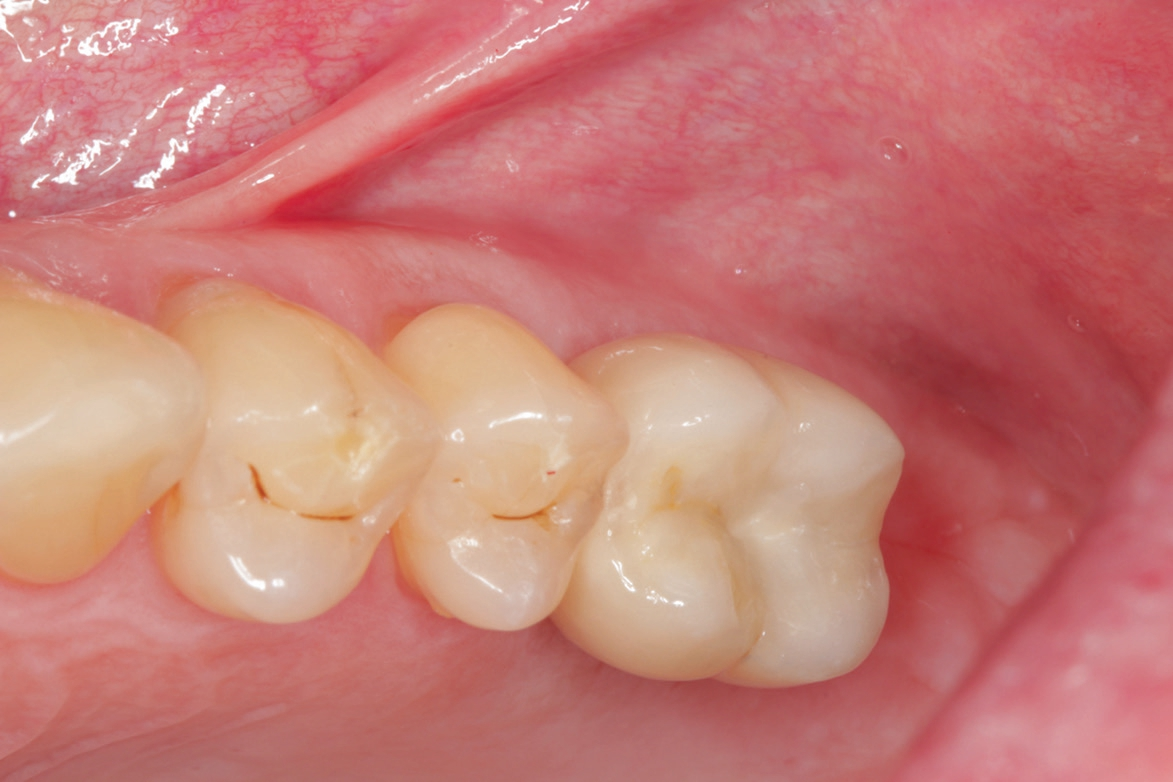

Vor Eingliederung der Krone wird die Hygienefähigkeit geprüft und sichergestellt, dass zukünftig in Okklusion und Artikulation keine traumatischen Kräfte auf die Restauration wirken. Nach Anziehen des erforderlichen Drehmoments wird der Schraubenkanal mit Teflonband gefüllt und ein okklusaler Verschluss mit Komposit vorgenommen.

Das durch die Kieferhöhle reduzierte Knochenangebot im Oberkiefer-Seitenzahnbereich erfordert eine veränderte Vorgehensweise in der Implantologie. Die Technik des internen Sinuslifts ist eine bewährte minimalinvasive Vorgehensweise, die jedoch, je nach Restknochenangebot und -qualität, ein Risiko in der Einheilphase für ein einteiliges Implantat birgt. Hier bietet das zweiteilige Pure Implantat eine perfekte Lösung, da bei gedeckter Vorgehensweise eine optimale Einheilung gewährleistet werden kann. In Kombination mit der bewährten, etwas modifizierten Variobase gelingt ein funktionell und ästhetisch ansprechendes Ergebnis.